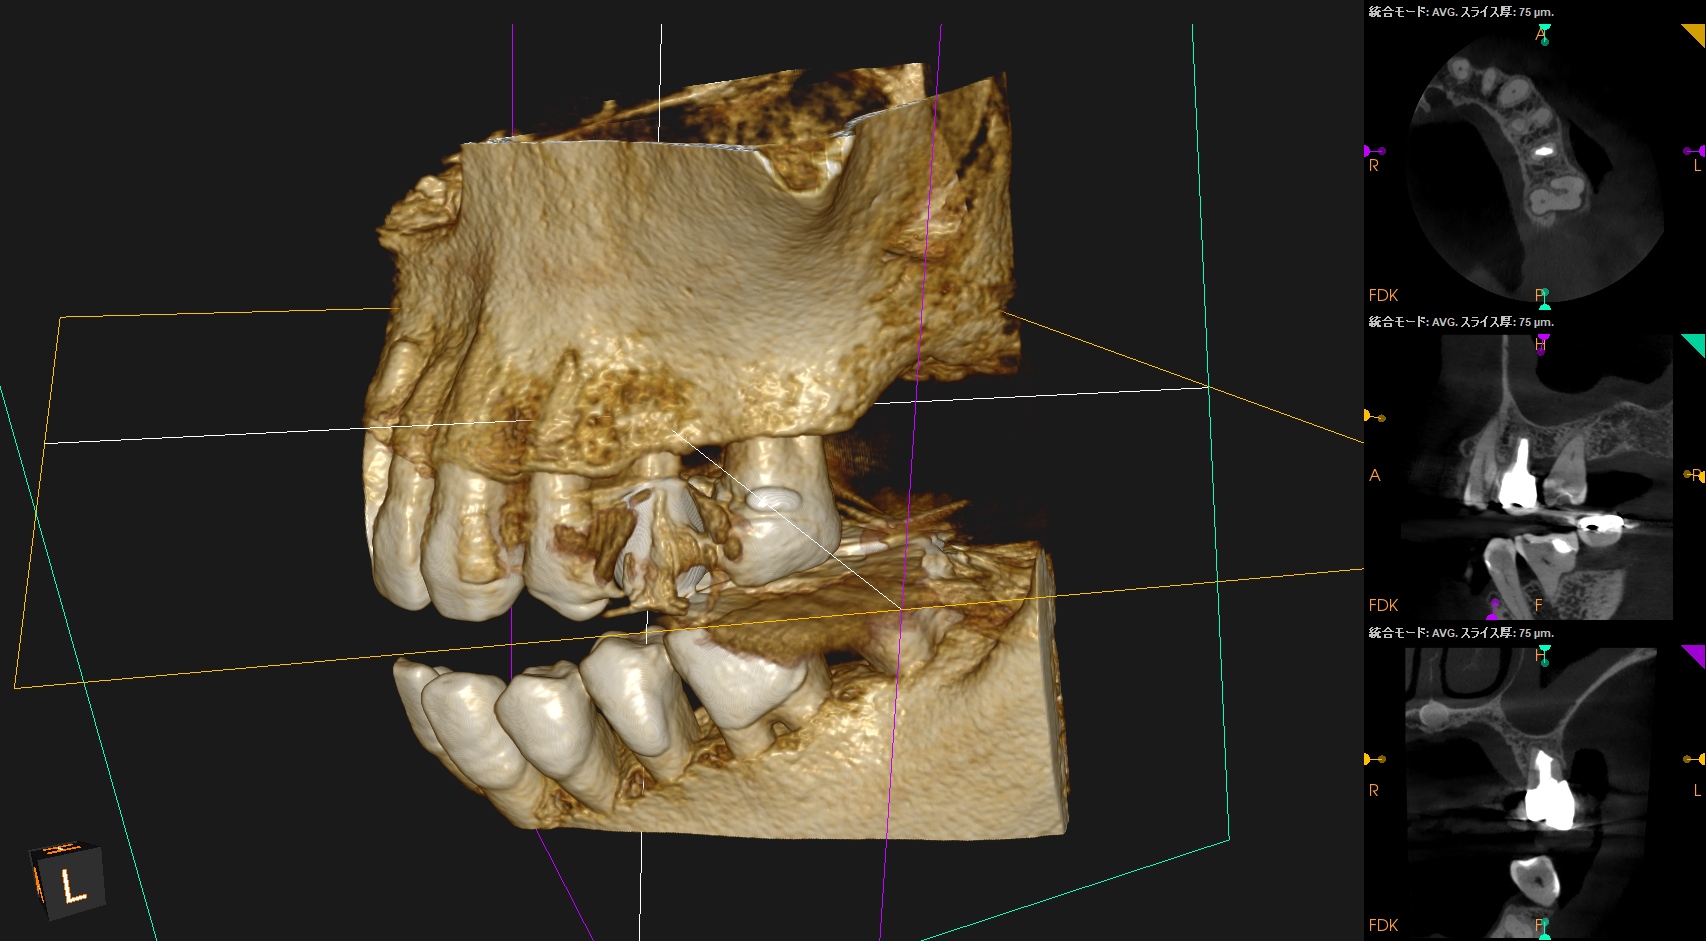

#13 Apicoectomy 1yr recall(2026.3.25)

1年前と比較してみた。

根尖病変は消失し、外科治療に関わる骨欠損も完治した。この状態ならセラミックに変えてもいいだろうが、術前の状態では無理である。

歯内療法は歯槽骨の再生が図れる唯一の歯科医療である。

これぞ再生療法だ。